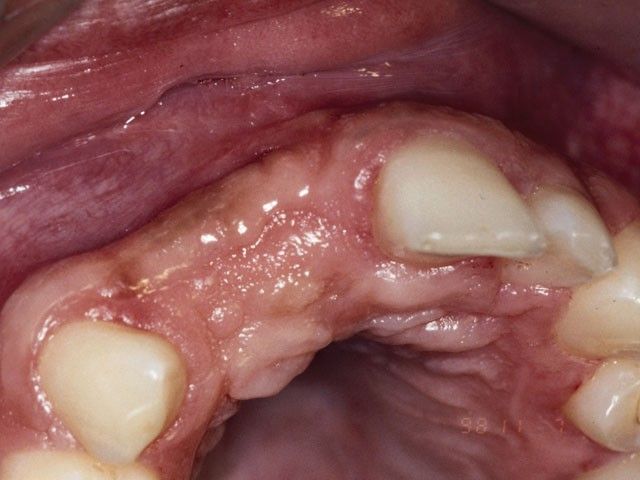

Από το 1992, ο χειρουργός οδοντίατρος Ιωάννης Μαρινάκης, στα Χανιά, ασχολήθηκε με τη χειρουργική τοποθέτηση εμφυτευμάτων και αναπλαστικών υλικών ιστικής και οστικής αναγέννησης.

Τη δεκαετία του 1990 αναπτύχθηκαν μέθοδοι με τις οποίες μπορούμε να επιτύχουμε μερική ανάπλαση των ιστών που συγκρατούν τα δόντια (περιοδόντιο) και μεγαλύτερη έως πλήρη ανάπλαση του φατνιακού οστού. Καθοριστικής σημασίας ήταν, αρχικά, η χρήση της ημιδιαπερατής μεμβράνης και στη συνέχεια των αυξητικών παραγόντων, προϊόντων υψηλής βιοτεχνολογίας.

Το περιστατικό στις φωτογραφίες είναι του 1998 και αφορά αποκατάσταση απώλειας δοντιών και οστού στην πρόσθια άνω περιοχή από τροχαίο ατύχημα: